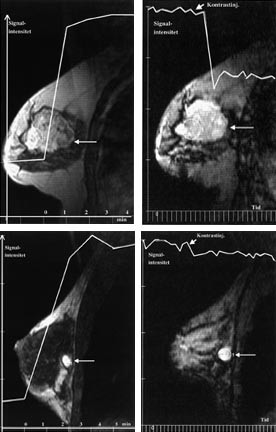

Det pågår en utstrakt forskningsaktivitet for å forbedre det diagnostiske potensialet til MR-undersøkelse av bryst. Ved MR-senteret i Trondheim har vi de siste årene særlig interessert oss for MR-teknikker som avspeiler kapillærgjennomblødningen i tumor, såkalt T2*-vektet førstepassasjebildedanning (fig 2). Bakgrunnen for å anvende denne teknikken er at kreftsvulster har flere og større kapillærer og dermed høyere kapillærperfusjon enn godartede svulster. Foreløpig synes det som om man ved denne teknikken kan påvise brystkreft med høy spesifisitet, men med en noe lavere sensitivitet enn den dynamiske T1-vektede teknikken (20). Siden T2*-vektet perfusjonsbildedanning avhenger av kapillærperfusjonen, kan metoden kanskje gi informasjon om tumorangiogenese (21) og dermed bli et hjelpemiddel både i vurderingen av kreftsvulstens metastaseringspotensial og i evalueringen av behandlingseffekten ved nye former for antitumorterapi som primært retter seg mot svulstens blodforsyning (antiangiogeneseterapi). MR-spektroskopi (MRS), hvor man benytter MR-teknikken til å få metabolsk informasjon fra svulsten, er en annen teknikk som i forskningssammenheng er brukt på brystsvulster. Metabolitten kolin, som inngår i cellemembranenes fosfolipidsyntese, er funnet i betydelige høyere konsentrasjoner i maligne enn i benigne brystsvulster, men det biokjemiske grunnlag for dette og den diagnostiske nytte av MRS i denne sammenheng trenger fortsatt evaluering (22, 23).

Brystkreftsvulster som er større enn 5 cm eller som vokser inn i hud eller brystvegg, behandles vanligvis med kjemoterapi eller anti-hormonbehandling før kirurgi. På grunn av problemer med å differensiere ødem og arrvev fra vitalt tumorvev er responsen på denne behandlingen vanskelig å vurdere, både klinisk og med konvensjonelle bildemetoder. Flere studier tyder på at kontrastopptak ved MR samsvarer godt med vitalt tumorvev (32, 33). Ved å registrere endringer både i kontrastopptaksmønster og tumorstørrelse er trolig MR den beste bildediagnostiske metoden for å evaluere behandlingseffekten (fig 4).